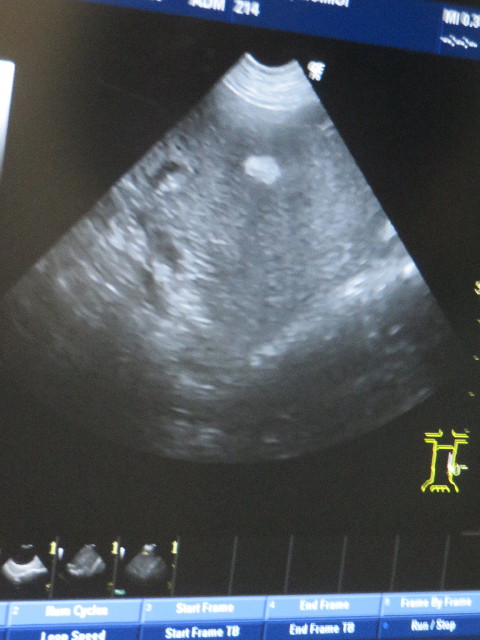

●2ケ月に1度してもらっている健康診断的エコー検査。

前と同じで、脾臓に組織が硬くなっているところがあります。(白く写っている所)

悪いものではないので経過観察です。